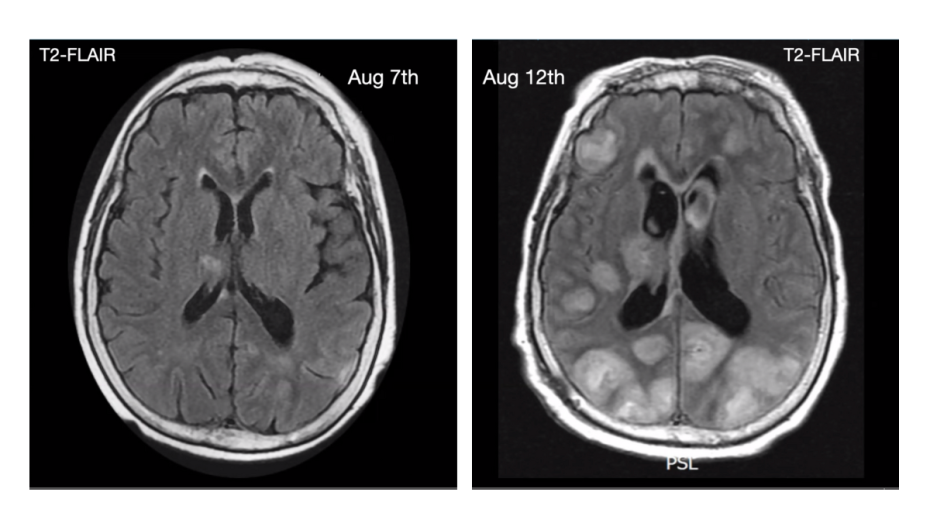

In his hour-long talk, punctuated by audience questions and more than a few laughs, DeRisi outlined his lab’s decade-long journey studying Balamuthia mandrillaris, an organism commonly known as a brain-eating amoeba because it causes severe brain inflammation. It is rare, but fatal and often goes undiagnosed.

Over a few years, DeRisi’s lab had the opportunity to test nitroxoline, with emergency Food and Drug Administration approval, for dire cases of brain inflammation caused by Balamuthia. The results were positive. DeRisi credits Heather Stone from the FDA for her advocacy in getting patient approvals.

They included a man in his 50s, seizing with a Balamuthia infection, and a six-year-old child, originally thought to have brain cancer, who turned out to have Balamuthia.